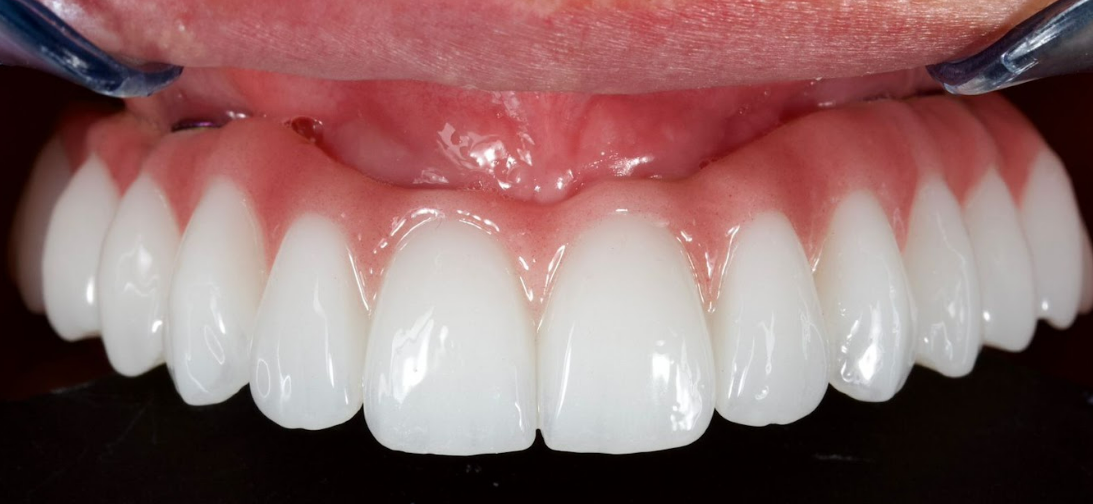

Next, using CAD/CAM technologies, a fixed, full-contour zirconia bridge was manufactured, designed for screw retention on titanium sleeves.

The final impression was performed using XGATE digital scan bodies, which made it possible to maintain a fully digital workflow at all stages of treatment.

The following images show the final treatment result. The patient expressed complete satisfaction with both the functional outcome and the aesthetic aspects of the restoration.